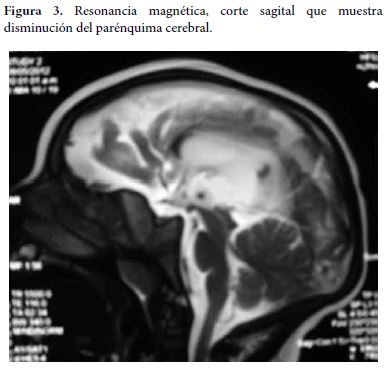

Se realiza una resonancia magnética de cerebro en donde se evidencia dilatación del sistema ventricular con circunvoluciones cerebrales escazas, además de agenesia del cuerpo calloso, considerando trastorno de migración neuronal (Figura 3 y 4).